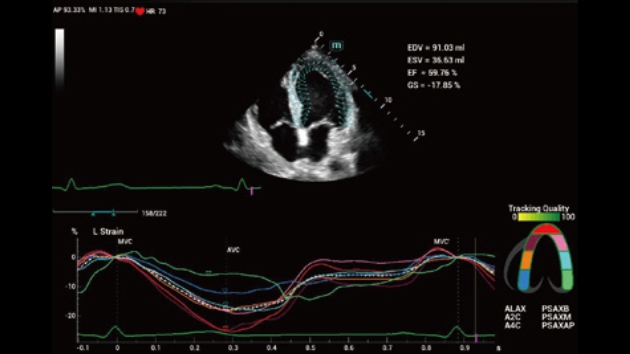

No matter your routine is in hospitals, clinics, or you are honing skills in General Imaging applications, women's health care or cardiovascular specialties, you will find highly powerful tools available on this series to keep you stay ahead.

Comprehensive Imaging Solutions Powered by ZST+

The ZST+ platform is an extraordinary innovation, representing an ultrasound evolution. Transforming ultrasound metrics from conventional beam-forming to channel data based processing. It overcomes the traditional trade-off limitation among spatial resolution, temporal resolution and tissue uniformity, delivering exceptional image quality for infinite imaging solutions with non-stop improvements.